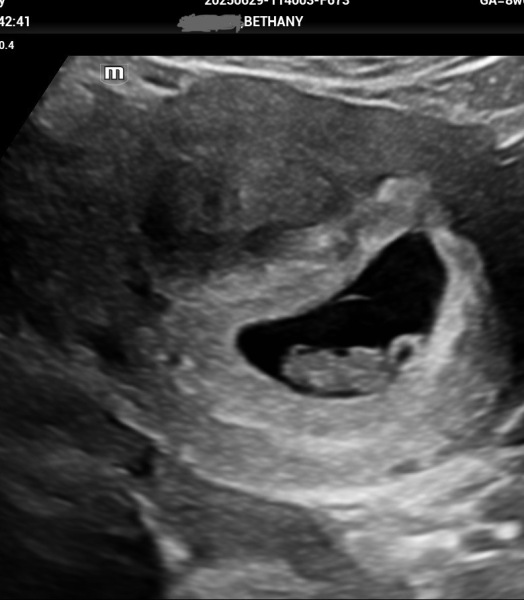

Boopbeep96 · 03/07/2025 23:11

Just another update, had an early assurance scan on Sunday at 8w2days and everything is perfect with baby. ❤️